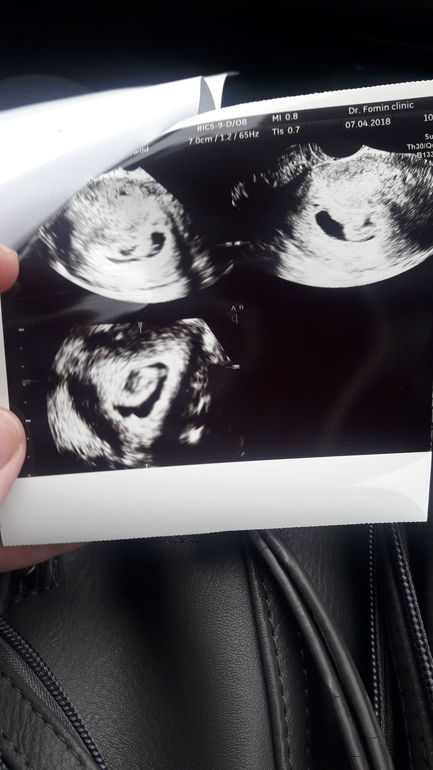

7 нед. Нет эмбриона.

Другой доктор сказала что после дмитриева она не спец. Посоветовала к лариной. В понедкльник поеду..только думаю что все...это не эмбрион он сказал...на фото..это не ясно что

сделайте УЗИ ещё дней через 5. У вас желточный мешочек есть, а это уже обнадёживает

Я ниже вам писала, что Дмитриев здесь считается отличным узистом, а жм у вас на прошлом узи был?может быть все таки рано?

Дождитесь понедельника, анэмбрионию я думаю он поставил, потому что плодное яйцо уже большое. верьте что будет чудо! Тем более такой светлый праздник завтра!!!

Кстати посмотрела узи в 7+1 у дочки и сына там такая же штука с неопределенными контурами